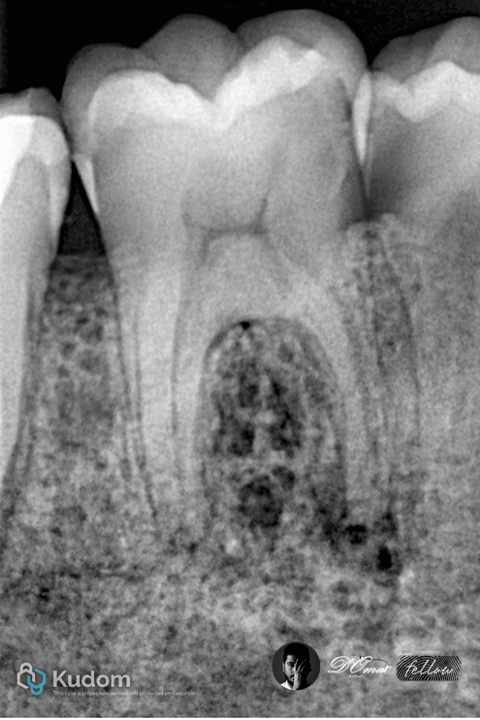

Fig. 5

Radiographic examination showed a well-defined periapical radiolucency associated with the mesial root.

Fig. 7

Mesial shift PA x-ray show the

6 canals ..6 oraface and 3 roots